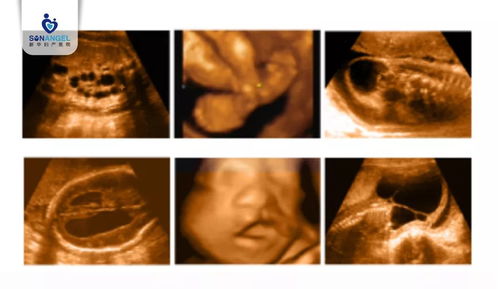

21周系统彩超主要包括以下几项检查内容:

胎儿头部:观察胎儿颅骨、脑室、脉络丛等结构,评估胎儿神经系统发育情况。

胎儿四肢:观察胎儿四肢的长度、形态,以及手指、脚趾的发育情况。

胎儿内脏:观察胎儿心脏、肝脏、肾脏、胃、肠道等内脏器官的发育情况。

胎儿脊柱:观察胎儿脊柱的连续性、形态,以及是否有脊柱裂等畸形。

胎盘、羊水:评估胎盘的位置、厚度、成熟度,以及羊水的深度、透声情况。